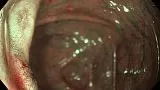

Пациент К.,60 лет, направлен на плановую колоноскопию с жалобами на длительную диарею и боли в правой подвздошной области, в анализах повышенный фекальный кальпротектин. На колоноскопии обнаружена одиночная язва у входа в илеоцекальный клапан , неправильной формы, с глубоким дном, на дне белый детрит, вокруг выраженные воспалительные явления, вокруг поверхностный рисунок при осмотре изменен, нерегулярный, взята биопсия. Илеоцекальный клапан не проходим для колоноскопа. На гистологии- язвенный дефект с дисплазией высокой степени, Болезнь Крона.

Колоноскоп- Olympus HQ-190. Осмотр  в режимах NBI  и  Near Focus.